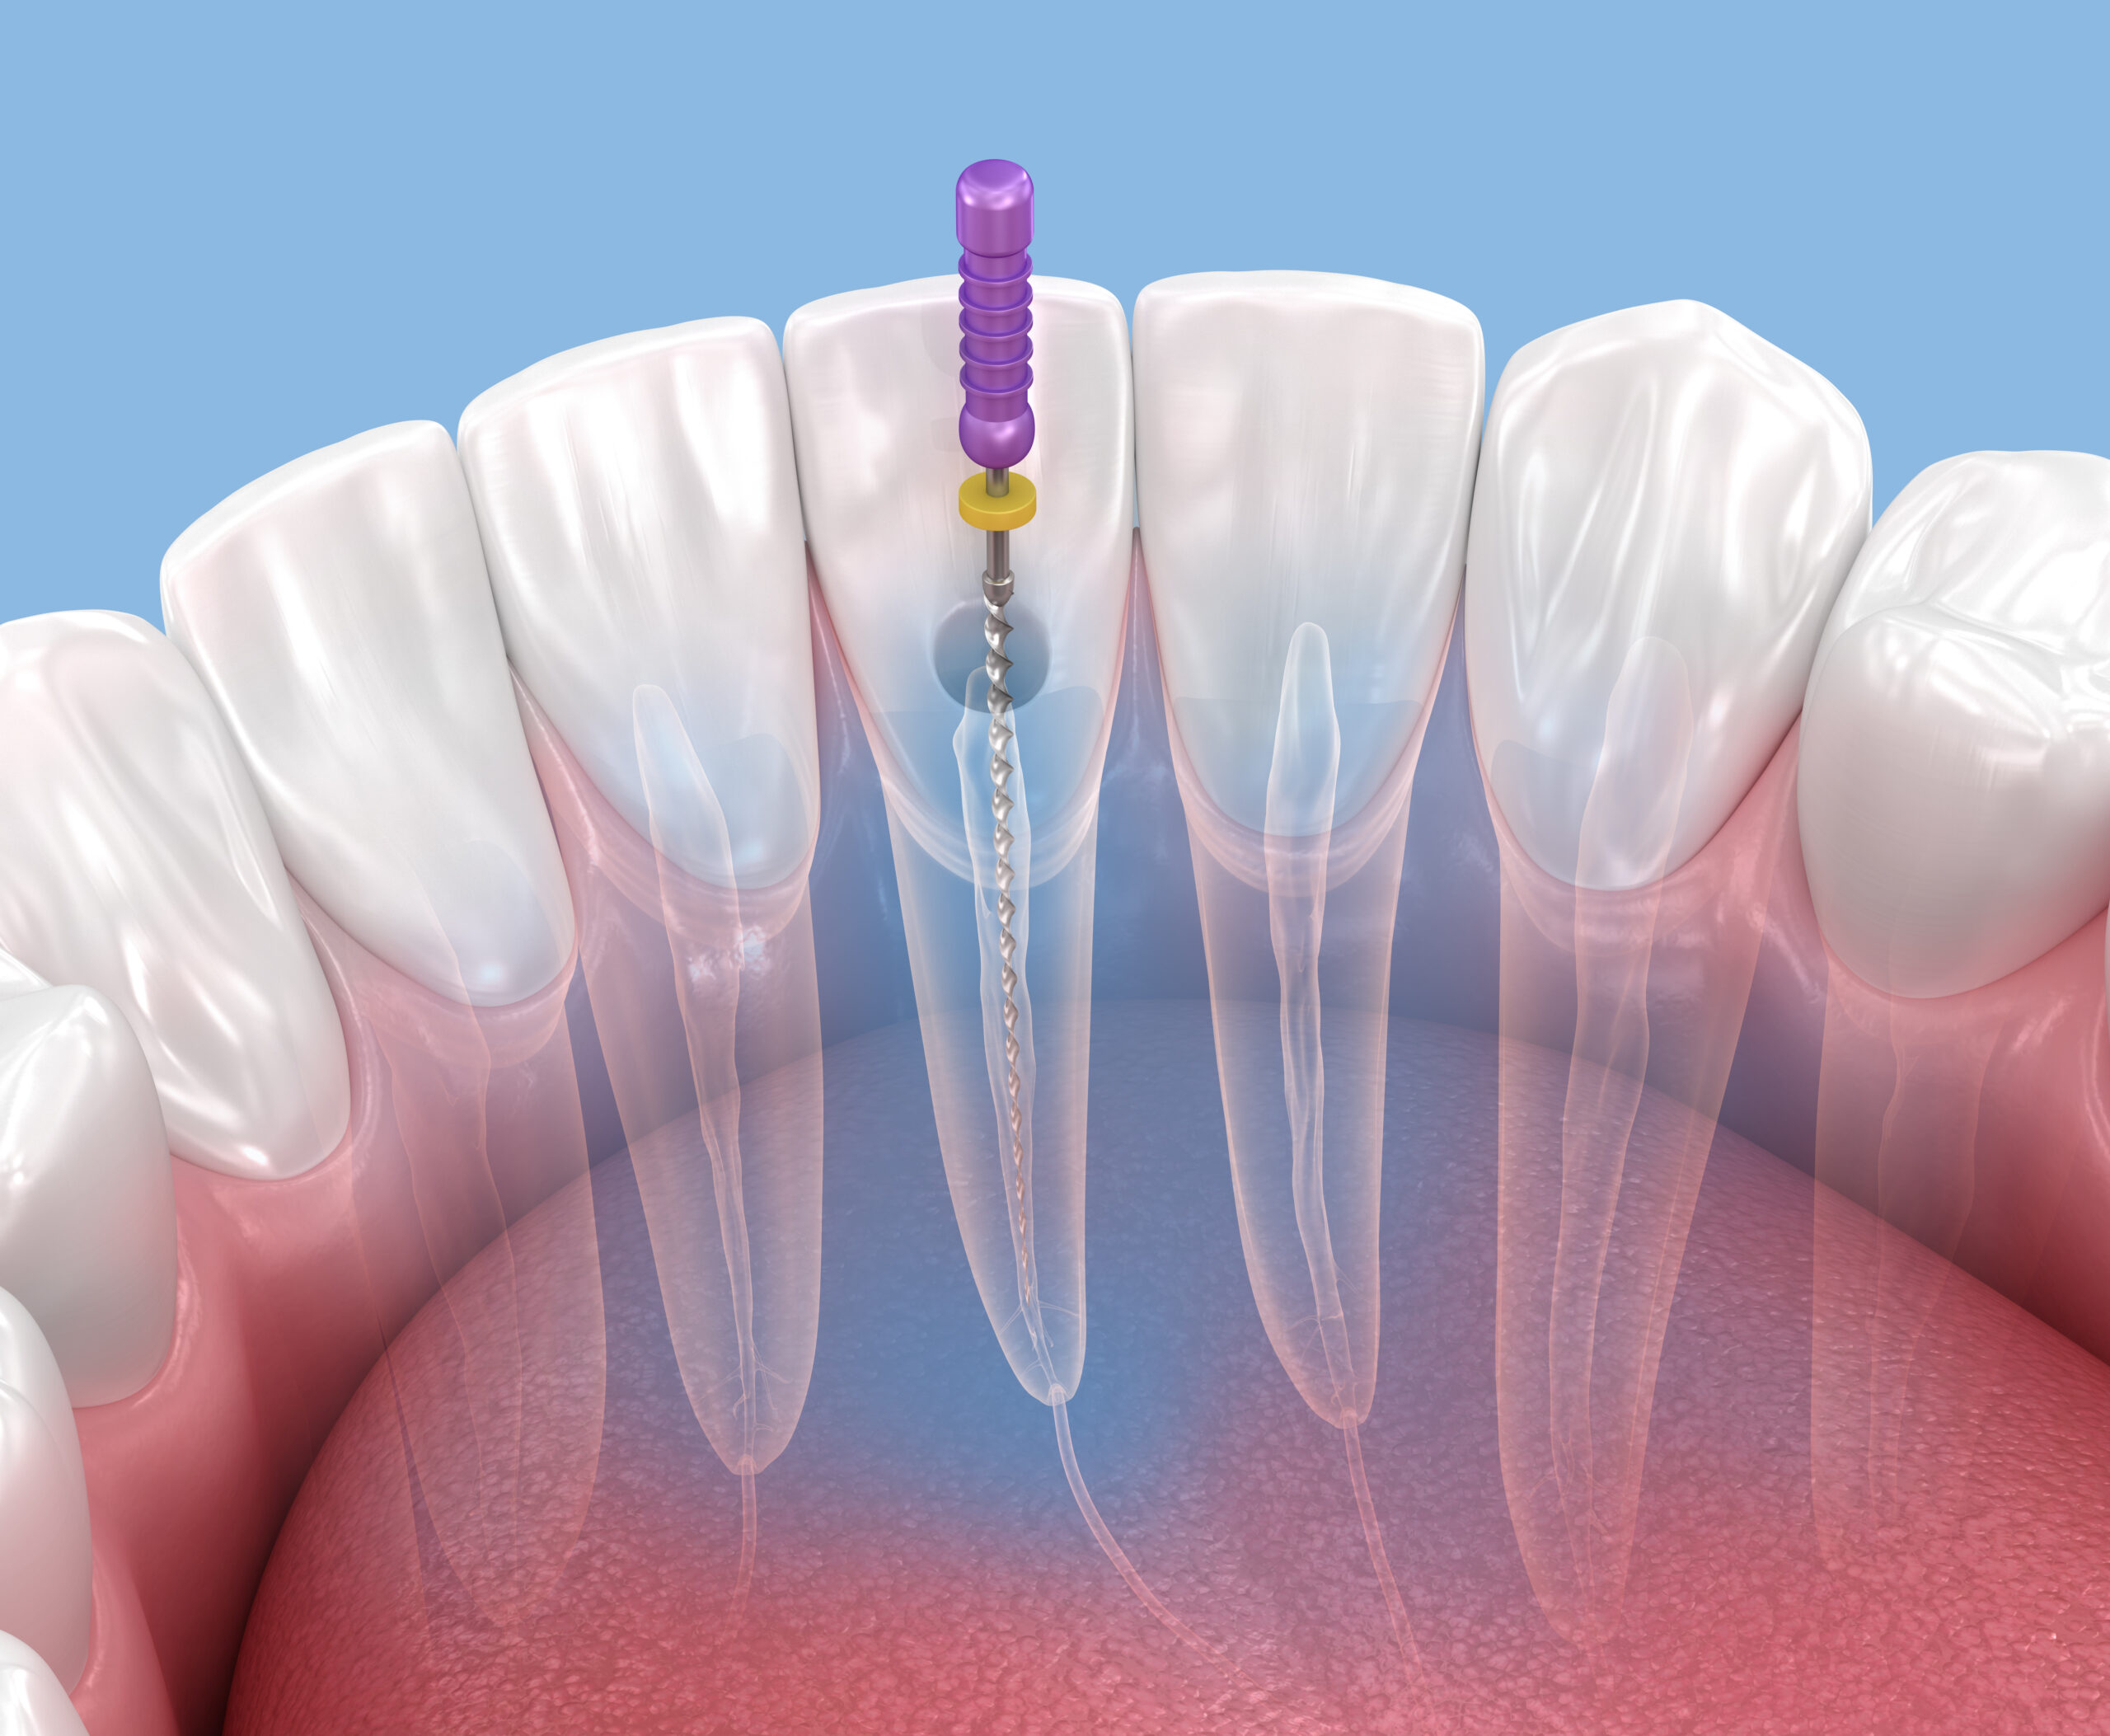

感染根管治療の基本的な流れは、以下の通りです。

- 診査・検査

- 感染部位を取り除く

- 根管内の洗浄・消毒を繰り返す

- 根管の中に薬剤を詰める(根管充填)

- 土台、被せ物の治療へ

感染部位を取り除く

虫歯になっている部分を取り除きます。被せ物や土台、過去の根管治療で詰めた材料がある場合はそれらを取り除き、専用の器具を用いて根管内の感染部分を取り除いていきます。

根管内の洗浄・消毒を繰り返す

根管内の細菌を除去するために、強力な消毒薬を用いて、根管内の洗浄と消毒を繰り返します。

根管の中に薬剤を詰める(根管充填)

洗浄と清掃によって根管内が無菌化されたら、専用の薬剤で根管内に隙間が無いように封鎖します。この処置は根管充填と呼ばれ、根管治療の最終段階の治療となります。